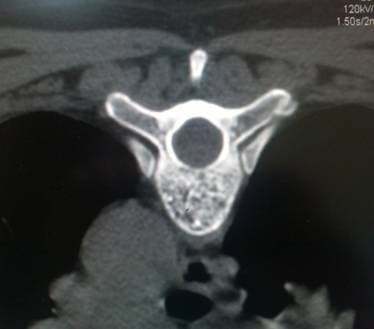

Гемангиома тела позвонка

Ячеистая структура тела позвонка при гемангиоме